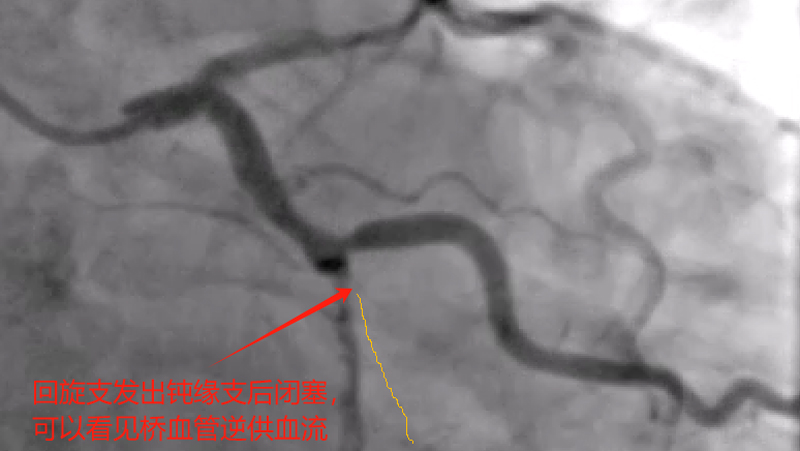

据了解,吴某,男性,58岁,因胸痛就诊,确诊为急性非ST段抬高型心肌梗塞,10多天前有过消化道出血情况,既往有心肌梗塞、痛风、慢性肾功能不全等病史,1年前胃镜提示有胃溃疡病史,口服有多种药物,考虑患者病情危重及复杂,心血管内科介入团队经过讨论后先行冠脉造影后再决定下一步诊疗策略,造影可见:前降支中段发出对角支后极重度狭窄,可见侧支循环右冠中远端,回旋支发出钝缘支后闭塞,可见钝缘支侧支循环回旋支远端;右冠中段闭塞。

经过医护人员精心照顾及治疗,患者各方面情况相对稳定,11月5日心血管内科介入团队再次为患者行冠脉介入治疗。并顺利开通右冠闭塞血管并植入支架恢复正常血流,同期解决前降支极重度狭窄病变并植入支架解除危机。手术总用时1小时40分钟,造影剂用量120ml。